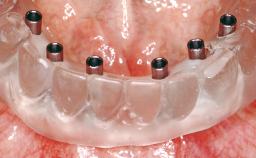

Immediate Loading of Eight Implants in the Maxilla and Six Implants in the Mandible and Final Restoration with Three-Unit and Four-Unit FDPs

Extensive scientific evidence has confirmed that immediately loaded implants with fixed full-arch provisional restorations can osseointegrate with success rates similar to conventionally or delayed loaded implants. A number of immediate-provisionalization techniques for edentulous jaws have been described. Some protocols differ when it comes to prefabricated provisional templates versus complete denture conversion; intrasurgical impressions versus direct relining; and cemented versus screw-retained provisional restorations. In this context, complete-denture conversion has been proposed for either intrasurgical impressions or direct relining. Another possibility is the utilization of a prefabricated provisional to be adapted either in the mouth (by direct relining) or in the laboratory (on a working model obtained from an intrasurgical impression).

Loading Protocol Immediate

Retention Cemented, with prosthesis margin < 3mm submucosal Cemented, with prosthesis margin < 3mm submucosal

Provisional Implant-Supported Prosthesis Prosthodontic margin < 3 mm apical to mucosal crest Prosthodontic margin < 3 mm apical to mucosal crest